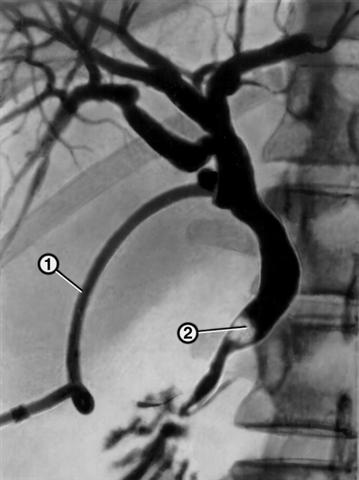

Рис. 3. Рентгенограмма, полученная при послеоперационной чреззондовой холангиографии у больного желчнокаменной болезнью: через зонд (1), введенный в общий желчный проток, заполнены контрастным веществом внутрипеченочные и внепеченочные желчные протоки, в дистальном отделе общего желчного протока виден дефект наполнения, обусловленный камнем (2).